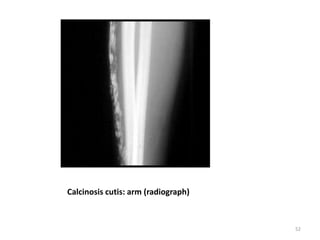

Calcinosis cutis: arm (radiograph)

Calcinosis cutis: arm(radiograph) 52